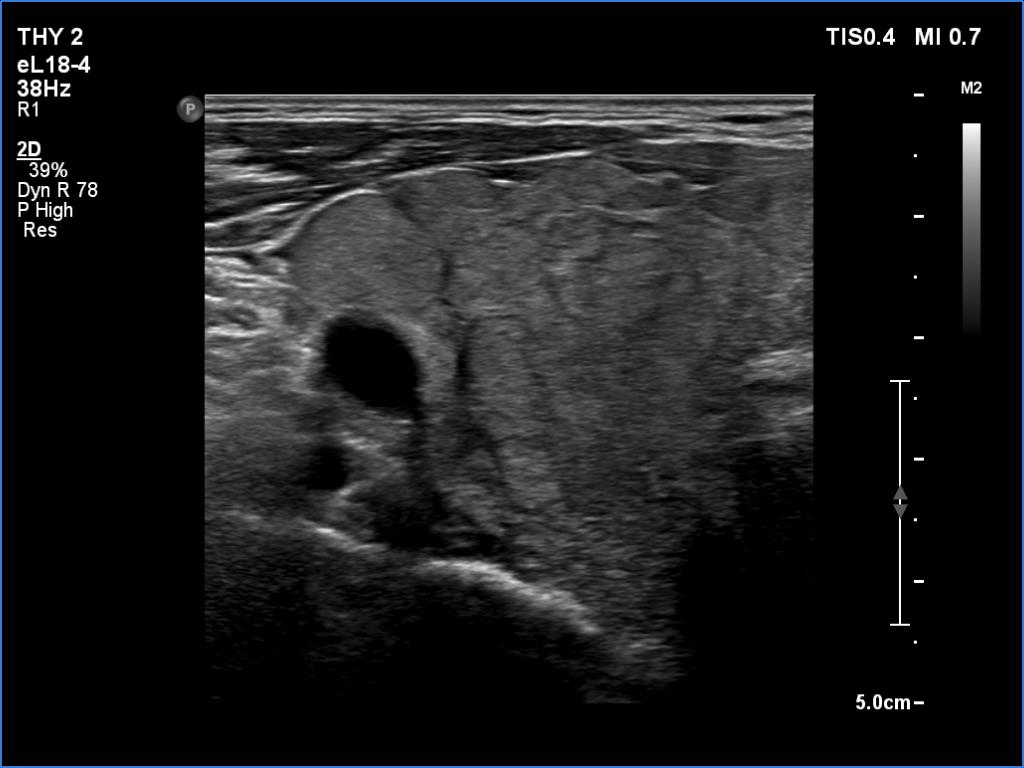

First examination (first row of images):

Clinical data: A 75-year-old woman was referred for evaluation of a goiter which was palpated by her GP.

Palpation: Both lobes were a bit firm and enlarged. There was a firm nodule in the isthmus.

Laboratory tests: TSH 4.49 mIU/L, aTPO 40 U/mL.

Ultrasonography. The thyroid was echonormal and had numerous discrete echonormal lesions. The largest of them was located in the isthmus. None of the lesions shared oncological importance.

Cytology was performed form the lesion in the isthmus and resulted in lymphocytic thyroiditis.

Suggestion: TSH and ultrasound in a year.